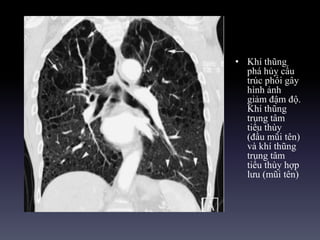

• Khí thũng

phá hủy cấu

trúc phổi gây

hình ảnh

giảm đậm độ.

Khí thũng

trung tâm

tiểu thùy

(đầu mũi tên)

và khí thũng

tiểu thùy hợp

lưu (mũi tên)

• Khí thũng pháhủy cấu trúc phổi gây hình ảnh giảm đậm độ. Khí thũng trung tâm tiểu thùy (đầu mũi tên) và khí thũng trung tâm tiểu thùy hợp lưu (mũi tên)